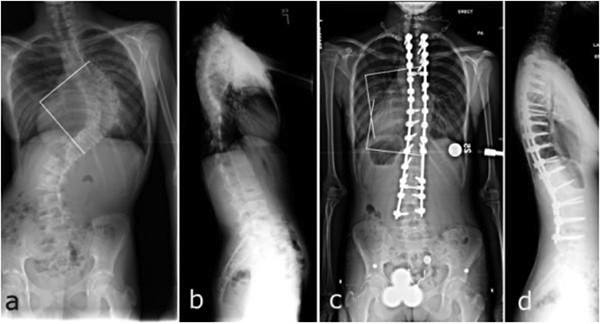

·Patient presentation 患者情况

19岁男性,发现高低肩2年,劳累后胸背部不适伴呼吸困难6月。

·Family and personal clincal history 家族史及个人史

既往体检,家族无相关疾病。

·Physical examination 体格检查

左肩高,双髂等高,左肩胛骨上移明显;无感觉异常,四肢肌力及活动度正常,腱反射正常,病理征阴性;

·Radiographic imaging 影像学检查

患者术前冠状面失衡严重

·Treatment 治疗方式 (术者:吴浩主任)

椎弓根螺钉植入,脊柱侧弯矫形术

治疗目的:减少青春期脊柱曲度增加,预防可能出现的呼吸障碍及脊柱疼痛,改善外观。

患者术后矫形良好